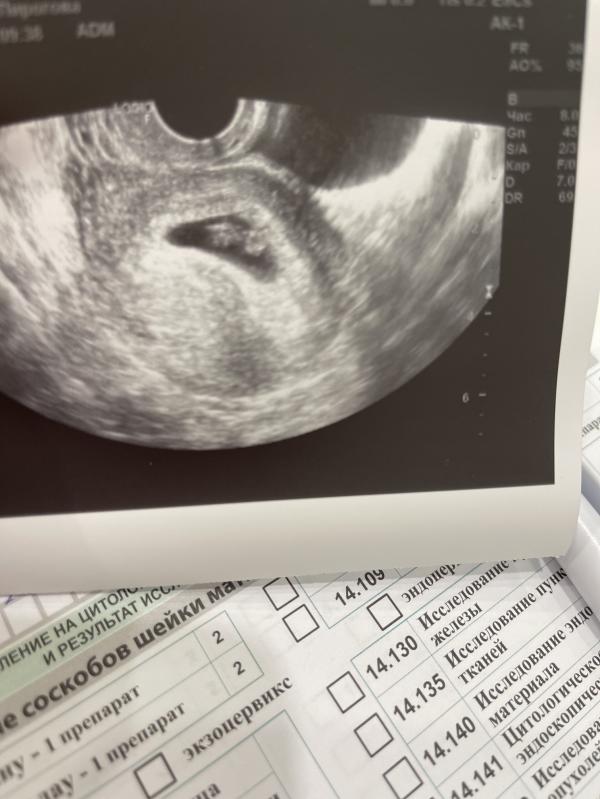

Неразвивающаяся беременность малого срока, хотели дать таблетки в стационаре «у вас нет эмбриона, беременность замерла»

Фото узи через 10 дней : есть эмбрион , есть сердечко ❤️

Беременную вовремя успокоила, отправила ждать. И вот результат 🙌